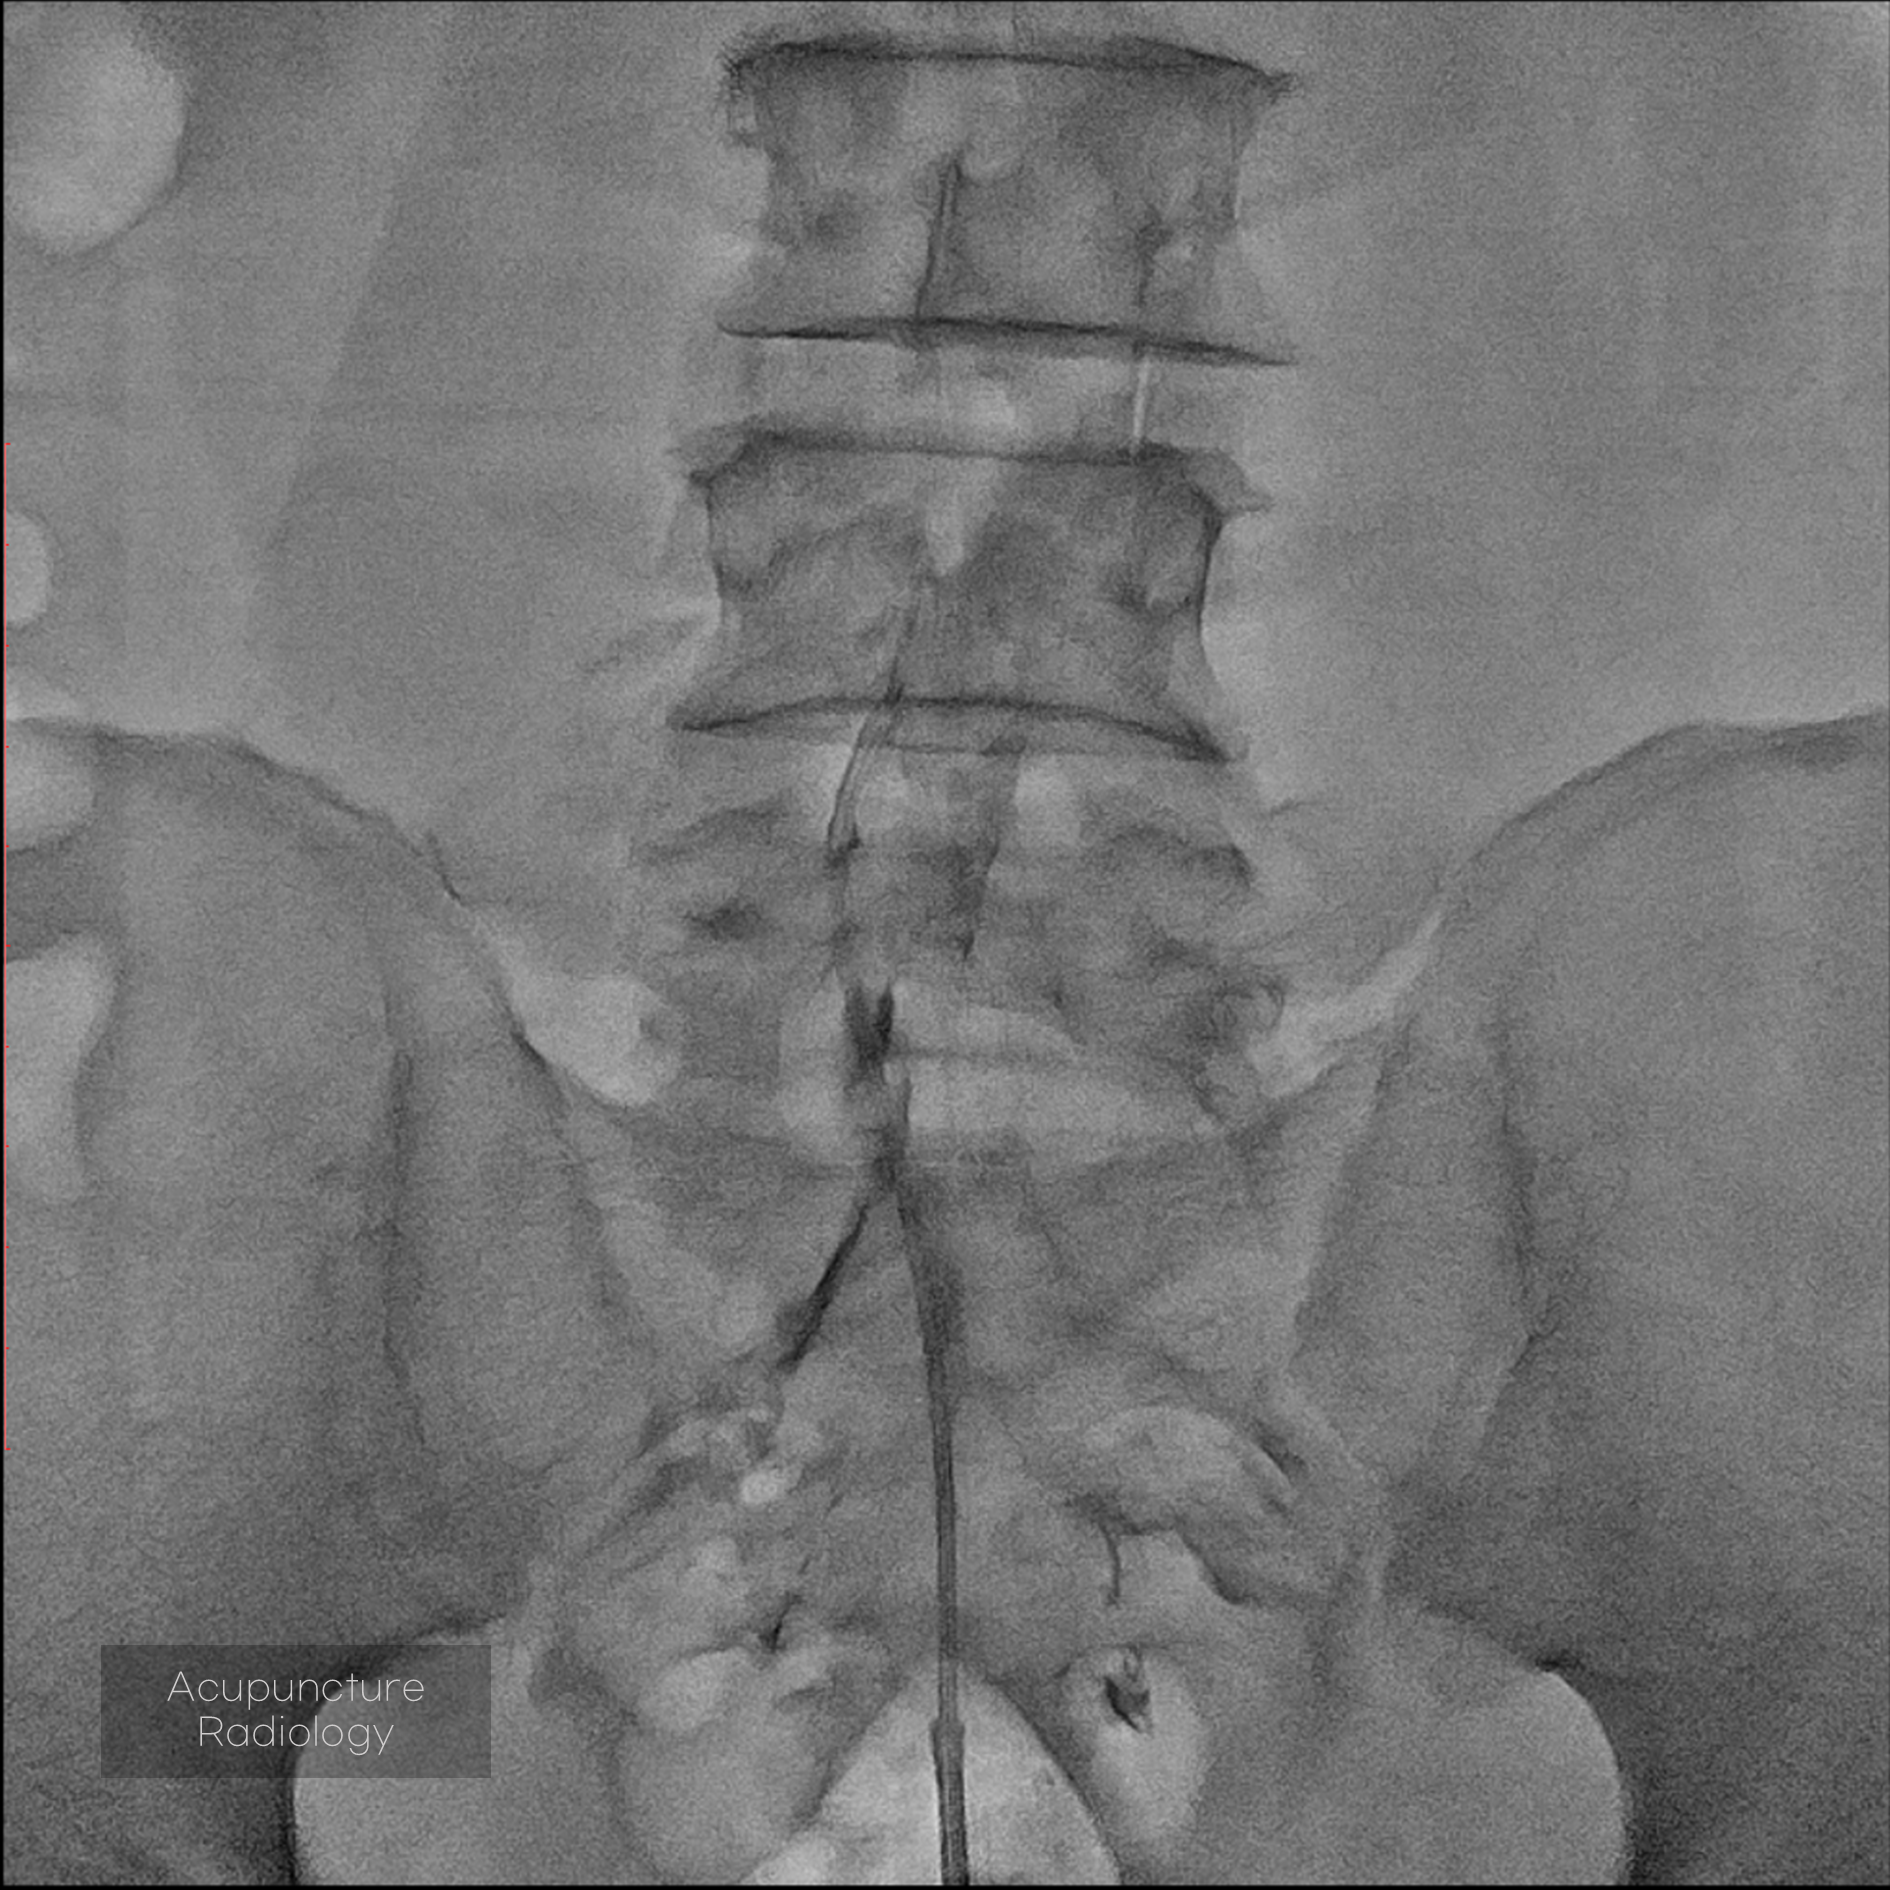

Editorial/Editor's Pick 경막외 유착박리술, Epidural Neuroplasty by Pharmacopuncture Research Lab 2026. 1. 3. 공유하기 게시글 관리 Acupuncture Radiology 관련글 MRI 요양급여의 적용기준 및 방법에 관한 세부사항 MRI 요양급여의 적용기준 및 방법에 관한 세부사항 [신구대조표] Association of AI‑determinedKellgren–Lawrence grade Portable X-ray